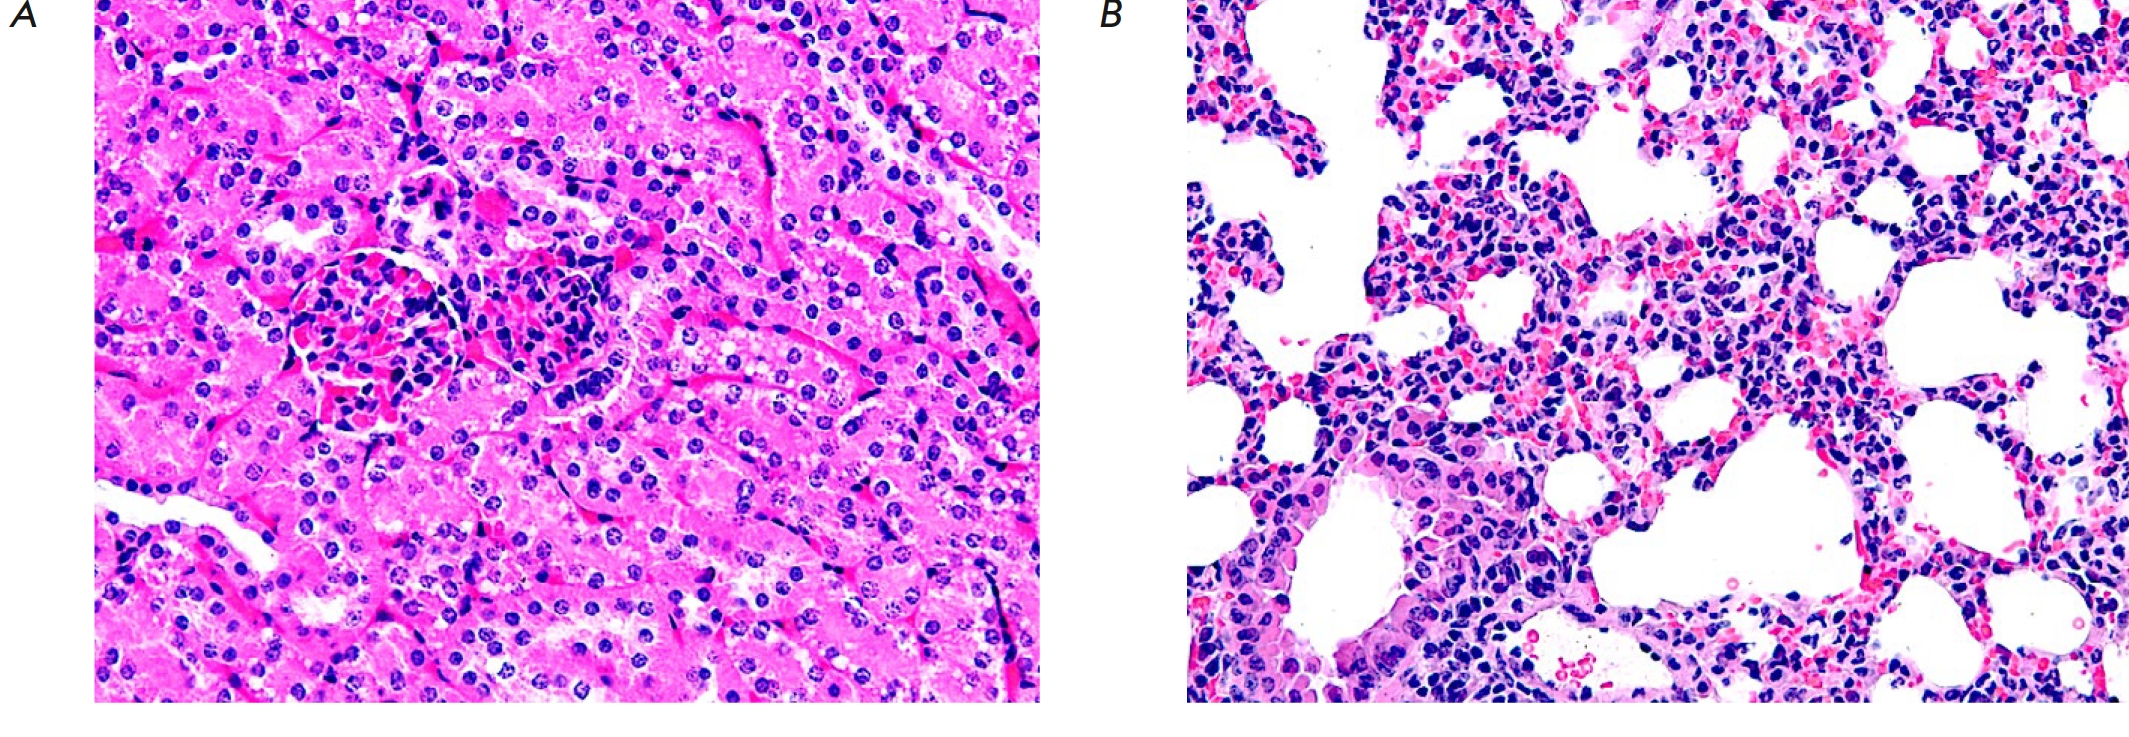

Fig. 2. A fragment of the mucous membrane of the wall of the stomach (A) and small intestine (B) in an experimental mouse after administration of 80 mg/kg 5'-noraristeromycin. Hematoxylin–eosin staining. 200× magnification

Administration of 5'-noraristeromycin at a dose of 80 mg/kg, which is close to the median lethal dose, to the animals induced pronounced changes in the histoarchitectonics of the analyzed organs and tissues. Hence, microscopic examination of the gastric wall revealed an activation of chief cells and mucoid cells, accompanied by gland dilation and accumulation of mucoid contents in them (Fig. 2A). Death and desquamation of numerous mucosal epithelial cells into the intestinal lumen was found when examining a small intestine fragment. The remaining villi became more flattened; their apical surface contained no fringe of microvilli. Thinning of the submucosa and partial reduction of the muscle and serous membranes were also observed (Fig. 2B).